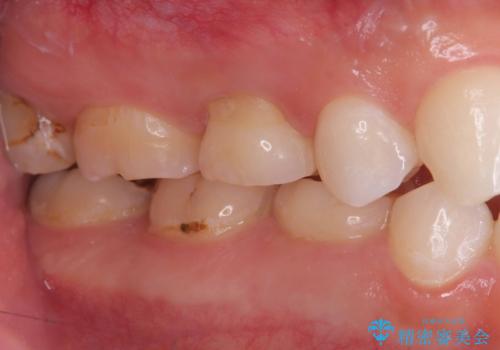

- 「歯がたまに痛む」を主訴に来院された患者様です。 見た目では齲窩が無いように見えますが、レントゲンを撮ると神経の近くまで達する深い虫歯だとわかりました。

虫歯を除去後セラミックインレーで治療を行いました。隣の子どもの歯のEも虫歯になっていたので同時に治療を行いました。

神経の近くまで虫歯が広がっていましたが、神経を保存して治療を行うことが出来ました。

見た目も凄く綺麗になり痛みも無く経過も良好なので、患者様も大変ご満足されていました。

Eに関してはCRで修復を行っています。